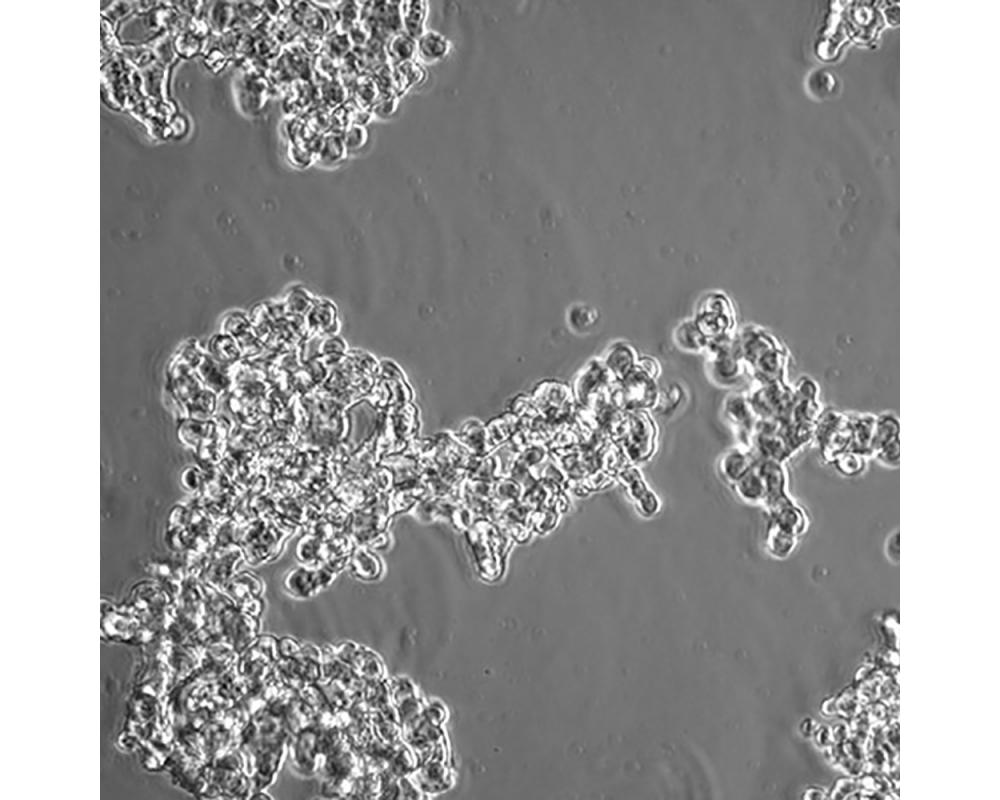

NCI-H526

產品名稱 NCI-H526

中文名稱 人小細胞肺癌細胞

組織來源 小細胞肺癌;骨髓轉移;男性

生長特性 懸浮